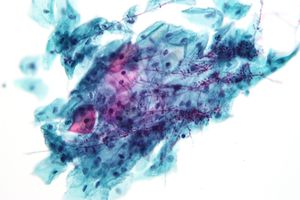

Cryptococcus

Cryptococcus. FNA specimen. Field stain.